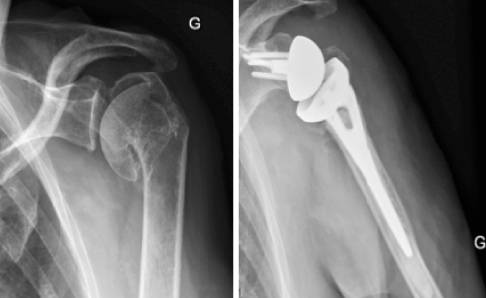

Protesi spalla

Protesi di spalla INVERSA: cos’è, come funziona, risultati, complicanze

La protesi inversa di spalla funziona sfruttando un meccanismo invertito rispetto alla protesi anatomica di spalla, attivando il movimento grazie alla funzione del muscolo deltoide.

Protesi inversa di spalla

La protesi inversa è una protesi di spalla “montata al contrario”, in cui la parte concava (inserto) viene adattata allo stelo omerale mentre la parte sferica costituisce l’impianto scapolare (glenosfera).